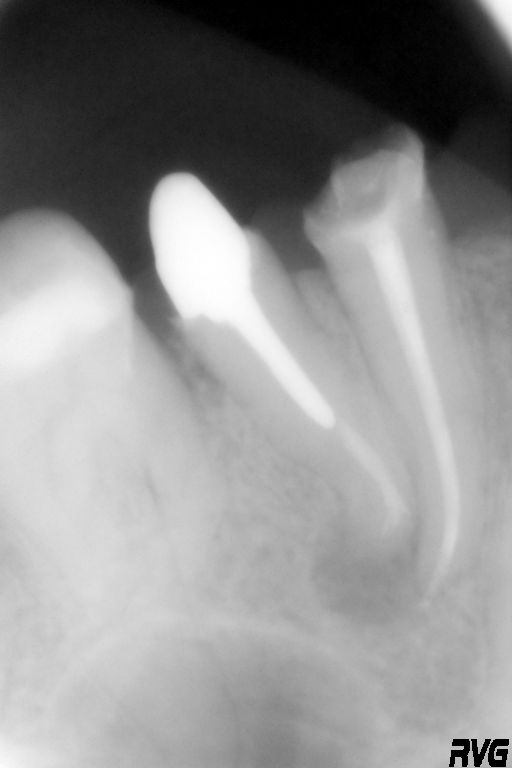

Хронический периодонтит может длительно себя не проявлять и обнаруживаться случайно на рентгеновском снимке при лечении соседних зубов.

Наличие инструментов в умелых руках – прибора для определения длины канала, ультразвука, диодного лазера — позволяет успешно проводить лечение периодонтита в одно посещение без применения антибиотиков и противовоспалительных препаратов. Подтверждением тому служит рентгеновский снимок, сделанный через несколько месяцев после окончания лечения (см. снимки с результатами лечения периодонтитов в нашей клинике — на этой странице справа).